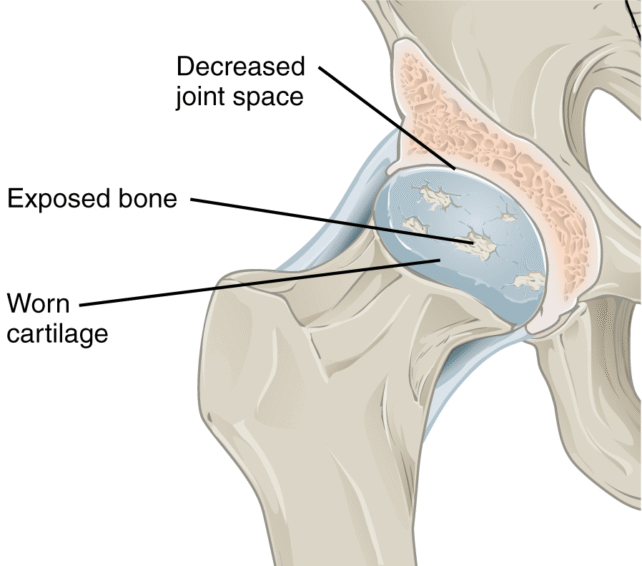

Obesity, metabolic disorders such as diabetes, and inflammation are major contributors to osteoarthritis progression. These conditions can affect just about every tissue in the body, including bone, cartilage, and synovium (the lubricating membrane lining the inner surfaces of joints).

Therefore, it seems obvious that weight loss eases osteoarthritis by reducing load-bearing forces on the joints. But this isn’t always the case. Existing osteoarthritis therapies are generally palliative. So while they may alleviate the symptoms, they don’t address the underlying cause.

But semaglutide appears to affect joint health at a fundamental level. In mice and humans with obesity and osteoarthritis, treatment with semaglutide reduced pain and decreased cartilage degeneration. Mice also had fewer bone spurs and less severe lesions in their joint membranes.